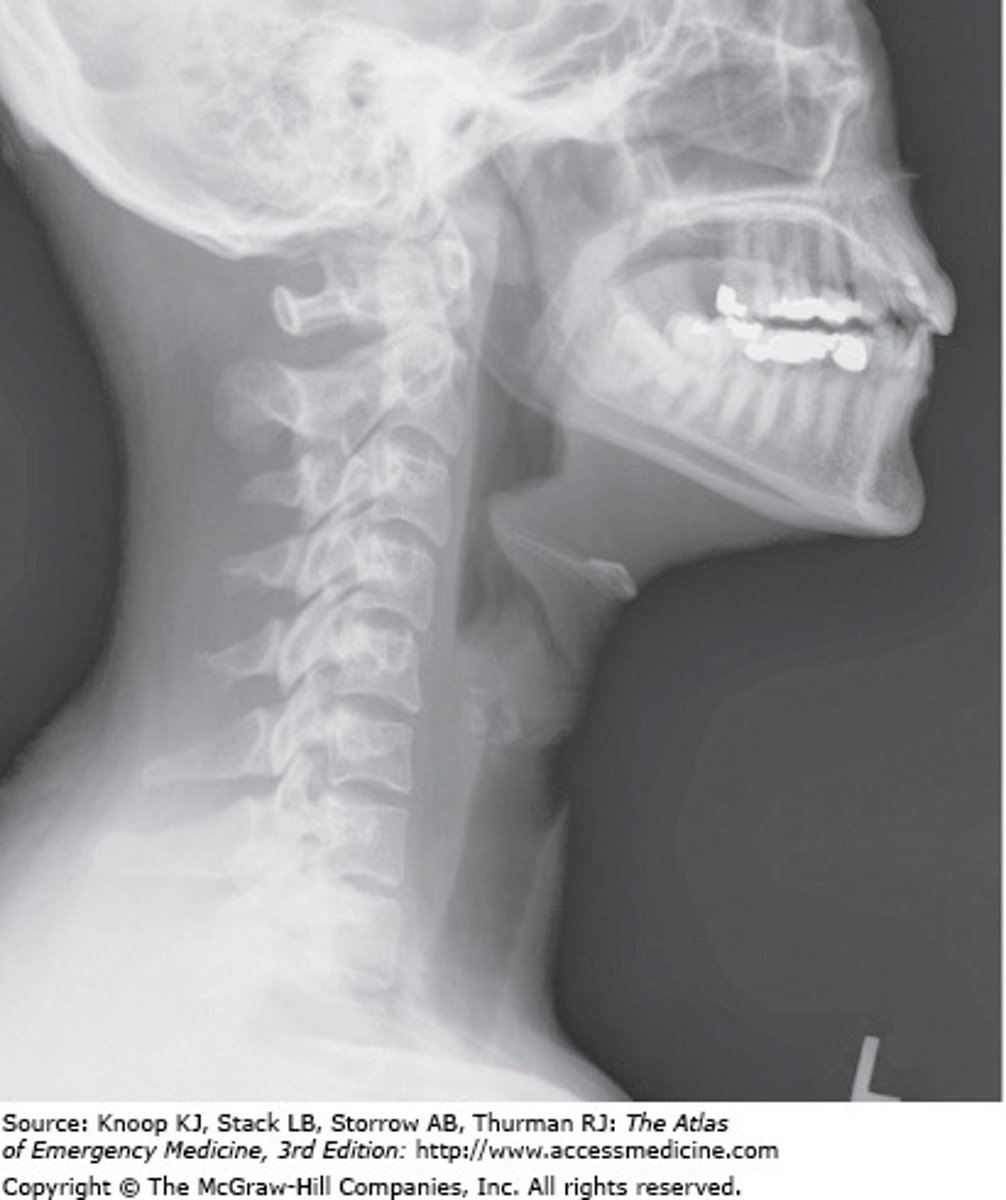

A soft tissue neck x-ray of a patient who complains of a progressively worsening sore throat reveals this lateral film (see image). Based on these findings, what is the initial treatment of choice for this patient?

The Correct Answer is: B

A 42-year-old healthy male presents to the emergency department with the complaint of a progressively worsening sore throat, and difficulty swallowing over the past 48 hours. He also complains of a subjective fever, but denies any headaches, nausea, or vomiting. On exam, the patient is afebrile and in mild distress, with a presentation of leaning forward on the exam table. His TM examination is normal, there is no rhinorrhea, and the oropharynx is patent without signs of stridor. His lungs are clear, and he has a regular rhythm on cardiac exam. What diagnostic test is indicated for a definitive diagnosis?

The Correct Answer is: D

This patient has a presentation that is consistent with acute epiglottitis. While ensuring that the airway is patent and the patient can maintain the airway, the first step in determining the diagnosis is a soft tissue neck x-ray, to determine inflammation to the epiglottis. While rare, epiglottitis can be from a bacterial infection, and can be quite serious and sometimes fatal.